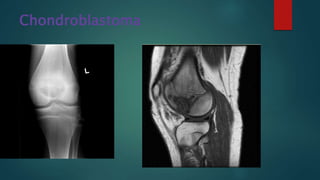

Chondroblastoma

• #88 1. A sharply defined lucent lesion is centred on the epiphysis of the distal femur, and appears to transgress the growth plate (which remains open). It has a narrow zone of transition and no convincing matrix calcification. Anteriorly it appears to abut the articular surface, possibly breaching it. A joint effusion is present. No periosteal reaction is present 2.Chondroblastoma in right lateral femoral condyle with low T1W and high T2W/STIR internal signal and surrounding bone marrow oedema